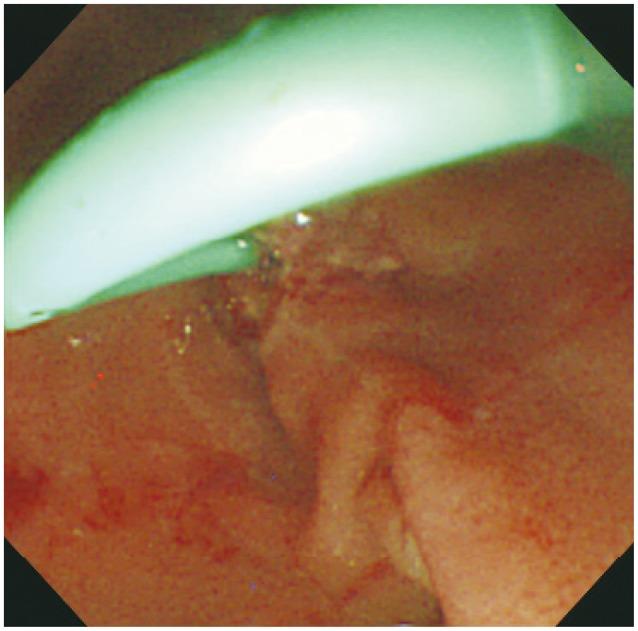

Pancreatitis is the most frequent and distressing complication of endoscopic retrograde cholangiopancreatography (ERCP). Many recent studies have reported the use of pharmacological agents to reduce post-ERCP pancreatitis (PEP); however, the most effective agents have not been established. Reduction in the incidence of PEP in high-risk patients has been reported through specific cannulation techniques such as guide wire-assisted cannulation and the use of pancreatic stents. The present review focuses on ERCP techniques for the prevention of PEP.

胰腺炎是内镜逆行胰胆管造影术(ERCP)最常见且令人困扰的并发症。许多近期研究报道了使用药物来降低ERCP术后胰腺炎(PEP)的发生率;然而,最有效的药物尚未确定。通过特定的插管技术,如导丝辅助插管和使用胰管支架,已报道高危患者的PEP发生率有所降低。本综述聚焦于预防PEP的ERCP技术。